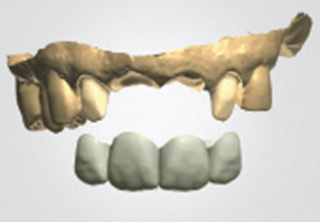

치료기간 단축

필요시 환자에게 적합한 임시치아를 미리 제작

하여 수술 당일 임시치아를 부착할 수 있으며,

시술 후 치유가 빨라 일반적으로 전체

치료기간이 줄어듭니다.

청담네오플란트 원데이 임플란트

하루만에 발치와 임플란트 식립을 동시에!

일반적으로 살릴 수 없는 치아를 발치하면, 2~3개월의 잇몸뼈 회복기를 거친 후 임플란트를 식립하게 됩니다. 하지만 잇몸뼈의 소실이

심하지 않은 경우 임플란트의 전체 치료기간 단축과 환자분의 불편감을 최소화하기 위해 내원 당일 발치 및 임플란트 식립을 진행할 수 있습니다.

필요에 따라 치조골 이식이 필요할 수 있으며, 가능한 경우 당일 임시 보철물 장착까지 해드려 심미적 기능을 회복할 수 있습니다.

발치 후 임플란트를 식립하고, 바로 임시 보철물을 제작함으로써 일상생활에서 불편감을 최소화할 수 있습니다.